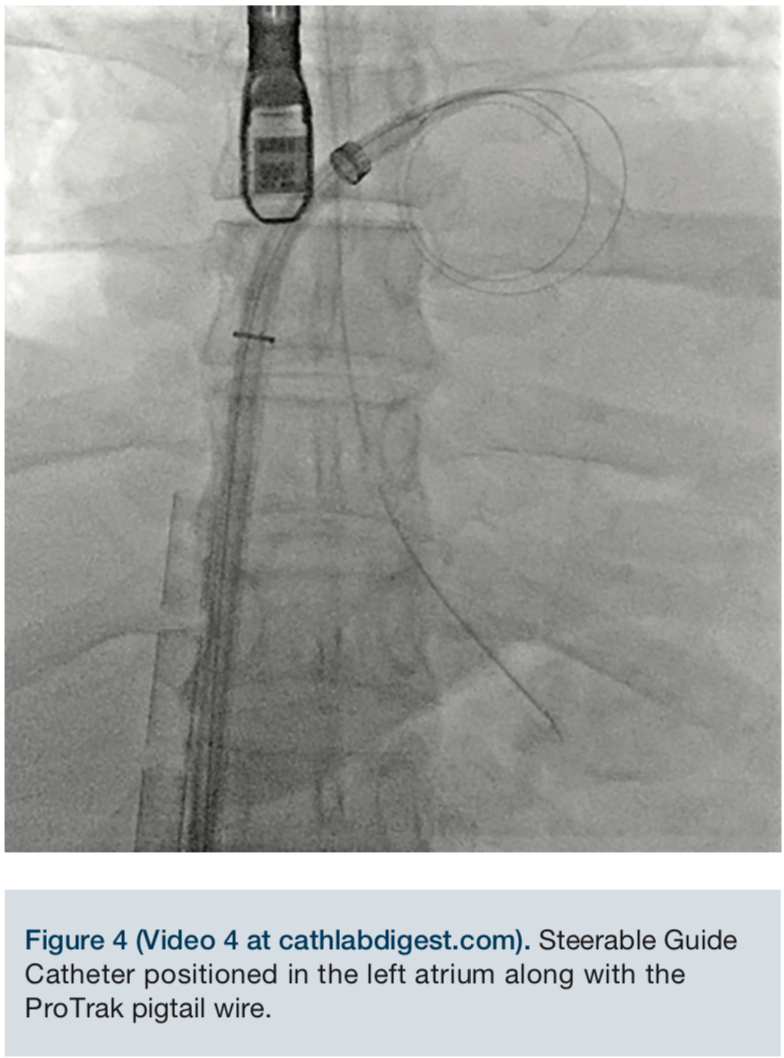

Video 4. Steerable Guide Catheter positioned in the left atrium along with the ProTrak pigtail wire.

Through a 6 French femoral venous sheath, an 0.032-inch Amplatz Extra Stiff guidewire (Cook Medical) was placed into the superior vena cava and the sheath removed. An 8 French SL1 sheath (St. Jude Medical) was advanced over the guidewire into the superior vena cava. Care was taken not to interfere with the ECMO cannula. Using standard technique under transesophageal guidance, the 71cm BRK transeptal needle (St. Jude Medical) was used to obtain a high and posterior puncture. The SL sheath was advanced into the left atrium. A ProTrack pigtail wire (Baylis Medical) was advanced into the left atrium. The 24 French steerable guide catheter was successfully negotiated across the intra-atrial septum and advanced into the left atrium using appropriate maneuvers.